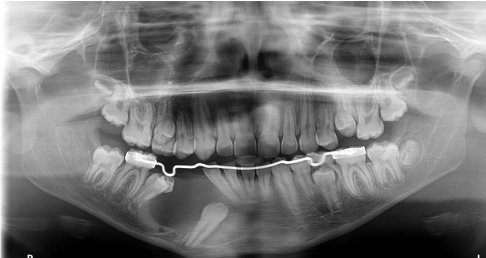

Case 4. A 9 years old male patient was sent to the attention of the specialist in the Department of Pediatric Odontostomatology and Orthodontics in the G.Gaslini Hospital from a freelance dentist because he has found in a Ortopantomography done for check the eruption progress a osteolytic lesion on the left side of the jaw.

On the ortopantomography multiple root leavings was found and a osteolytic mandibular lesion in the apical area of the 7.4 with dislocation of permanent teeth compatible with a diagnosis of dentigeruous cyst.

Marsupialization and biopsy was performed and a lingual arch is applied to maintain the space for erupting teeth. After three, six and nine months from the marsupialization ortopanthomography was done til to the eruption of the involved tooth (Figures 13-15).

Figure 13 Case 4. Three months after the marsupialization

Figure 14 Case 4. Six months after the marsupialization

Figure 15 Case 4. After nine months the involved teeth were erupted